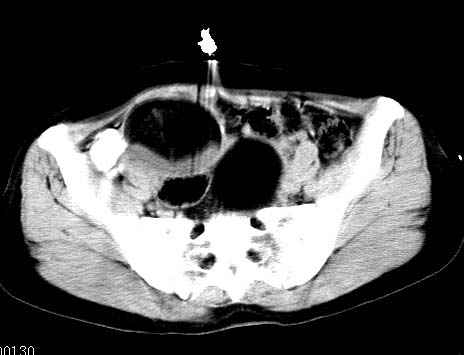

女性 病人 44岁 盆腔 下腹部痛1天!

盆腔内低密度为主混杂等密度及少许囊样与班状钙化影,如果做了肠道准备就好了。支持畸胎瘤。当然做mri会更好

典型的双侧附件畸胎瘤.

支持各位大侠观点.病人有急性腹痛,需除外有扭转可能.建议mri.

盆腔多发畸胎瘤,较为典型。